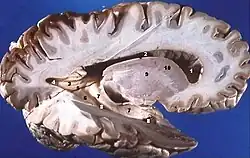

Sagittalschnitt des Gehirns: graue Substanz außen und weiße Substanz innen.